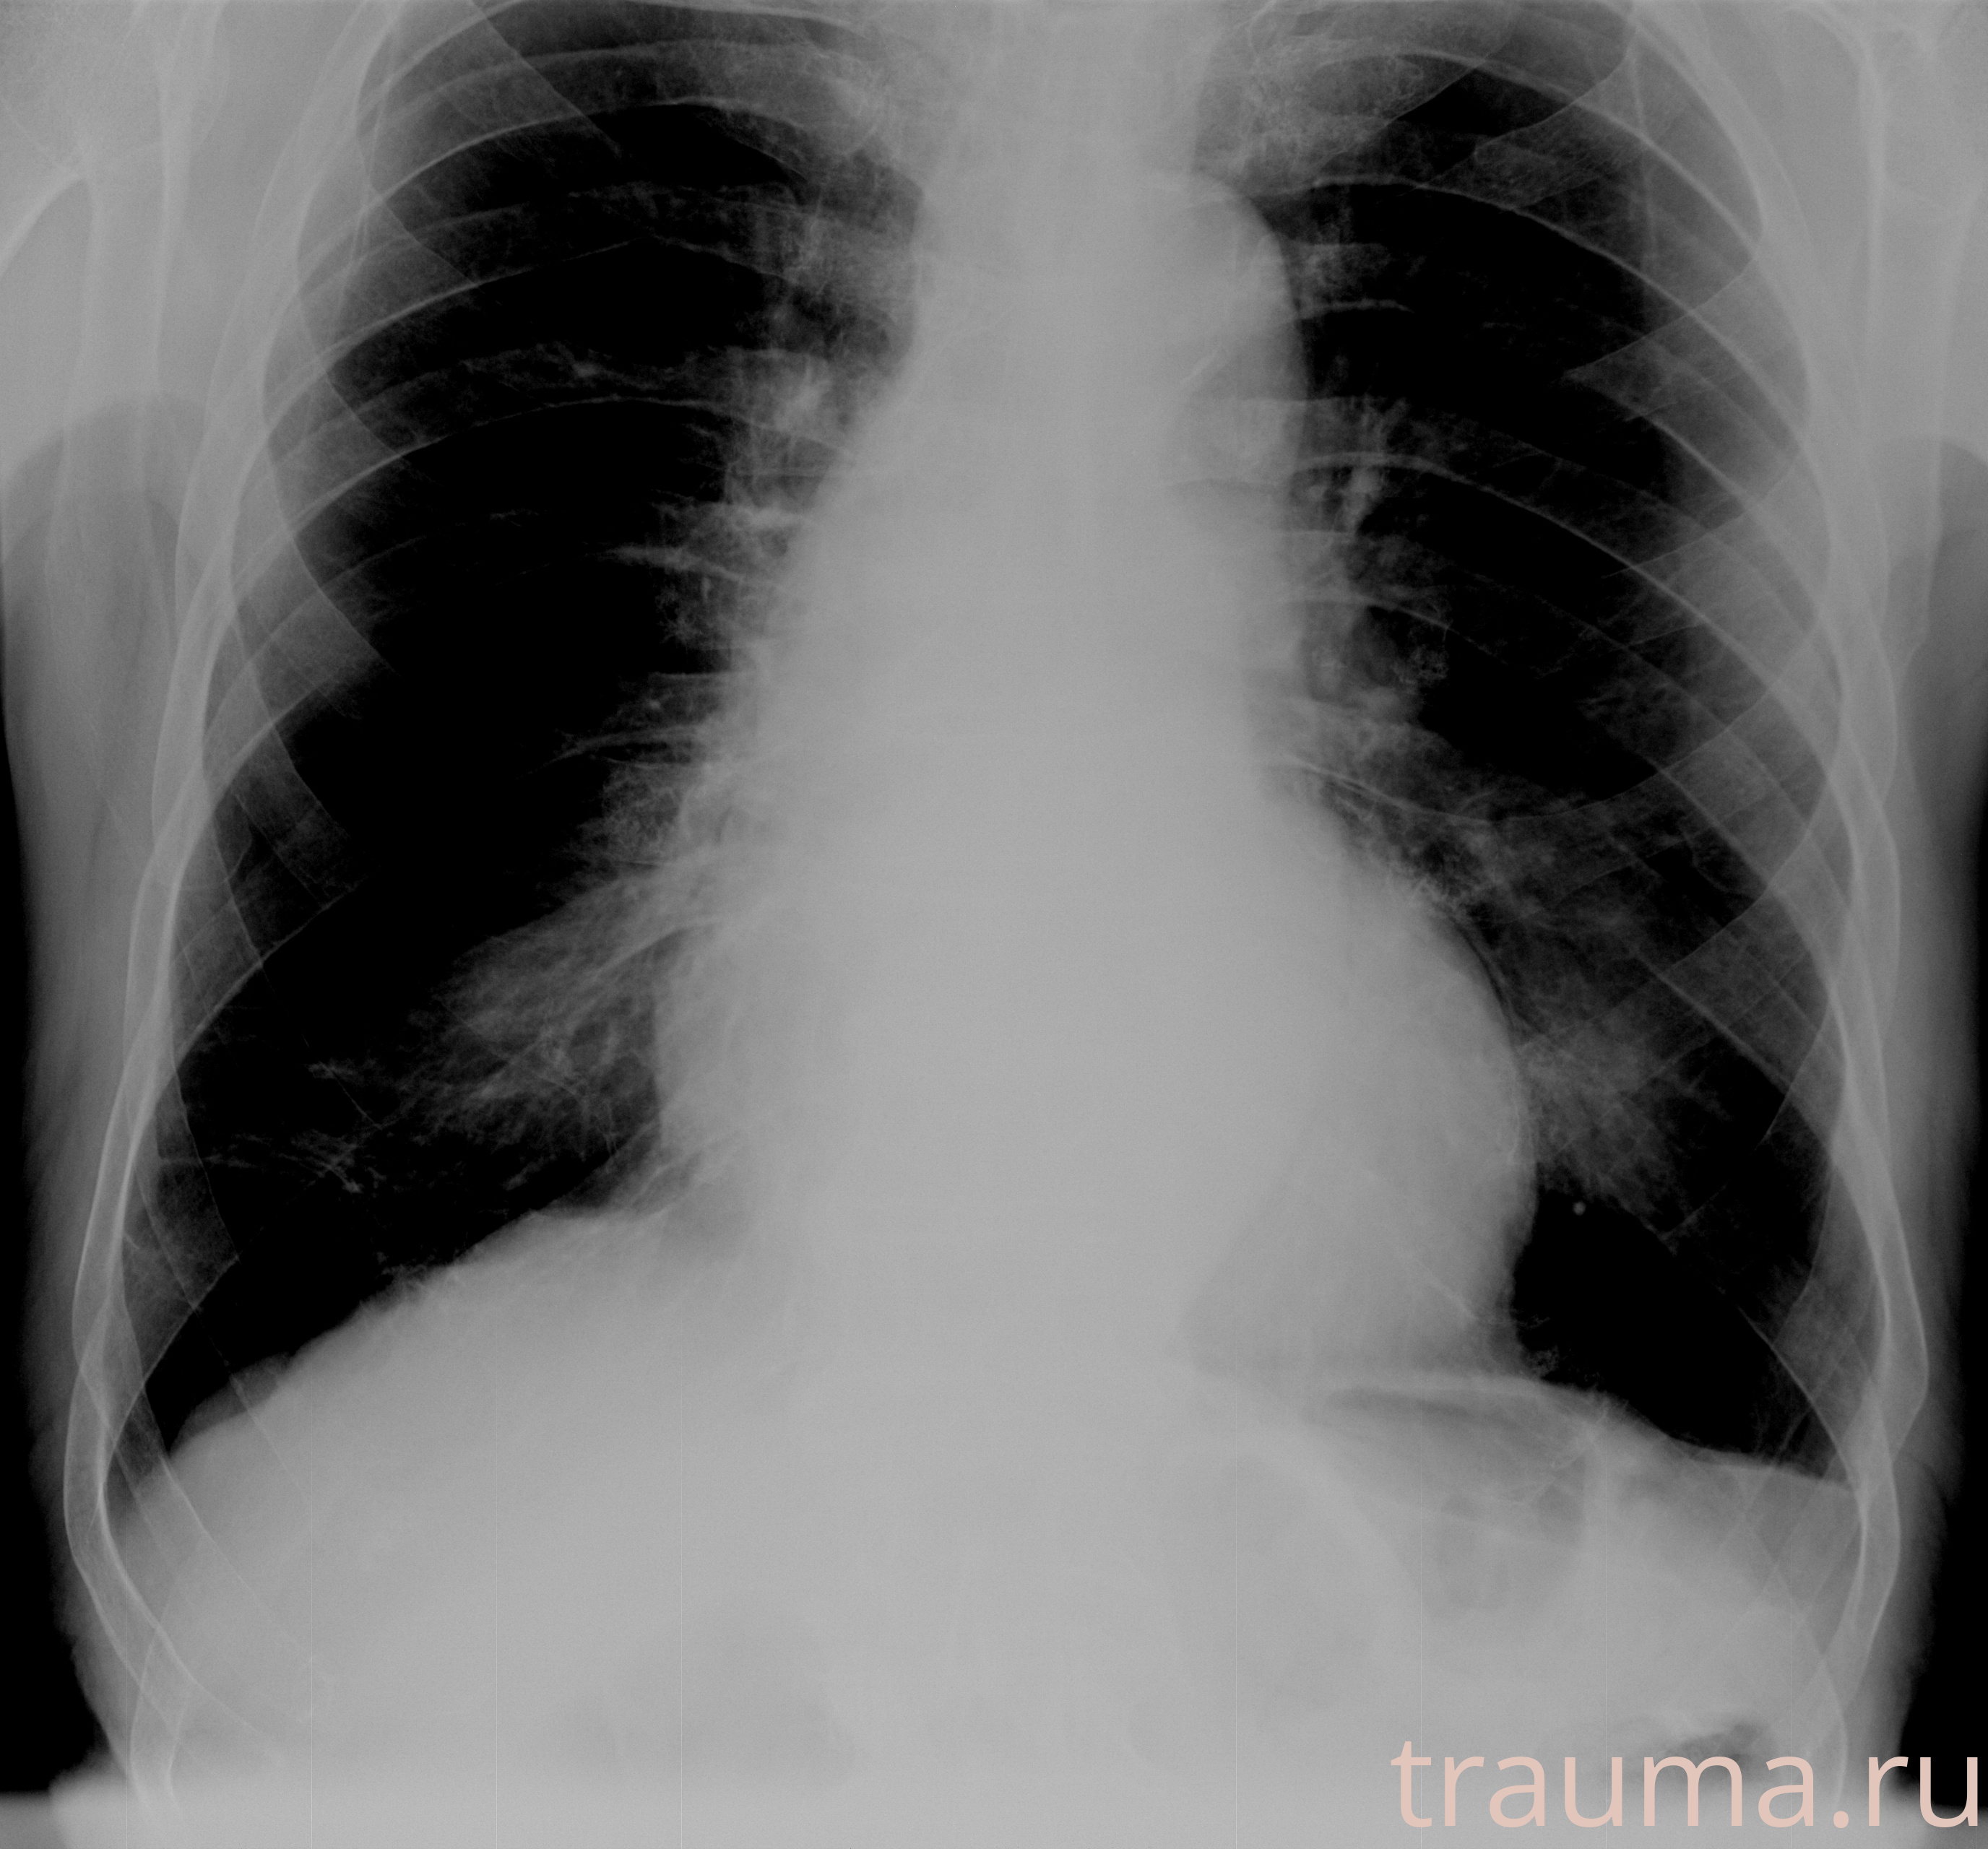

Рентген на дому: по вашему адресу приезжает врач-рентгенолог, травматолог-ортопед с мобильным рентгеновским аппаратом, проводит диагностику травмы или заболевания, делает необходимые рентгенограммы, дает рекомендации по дальнейшему лечению. Получить качественные снимки в домашних условиях возможно благодаря уникальной методике, разработанной МосРентген Центром для института  Склифосовского

при переломе шейки бедра и пневмонии от компании МосРентген Центр - партнера Института имени Склифосовского